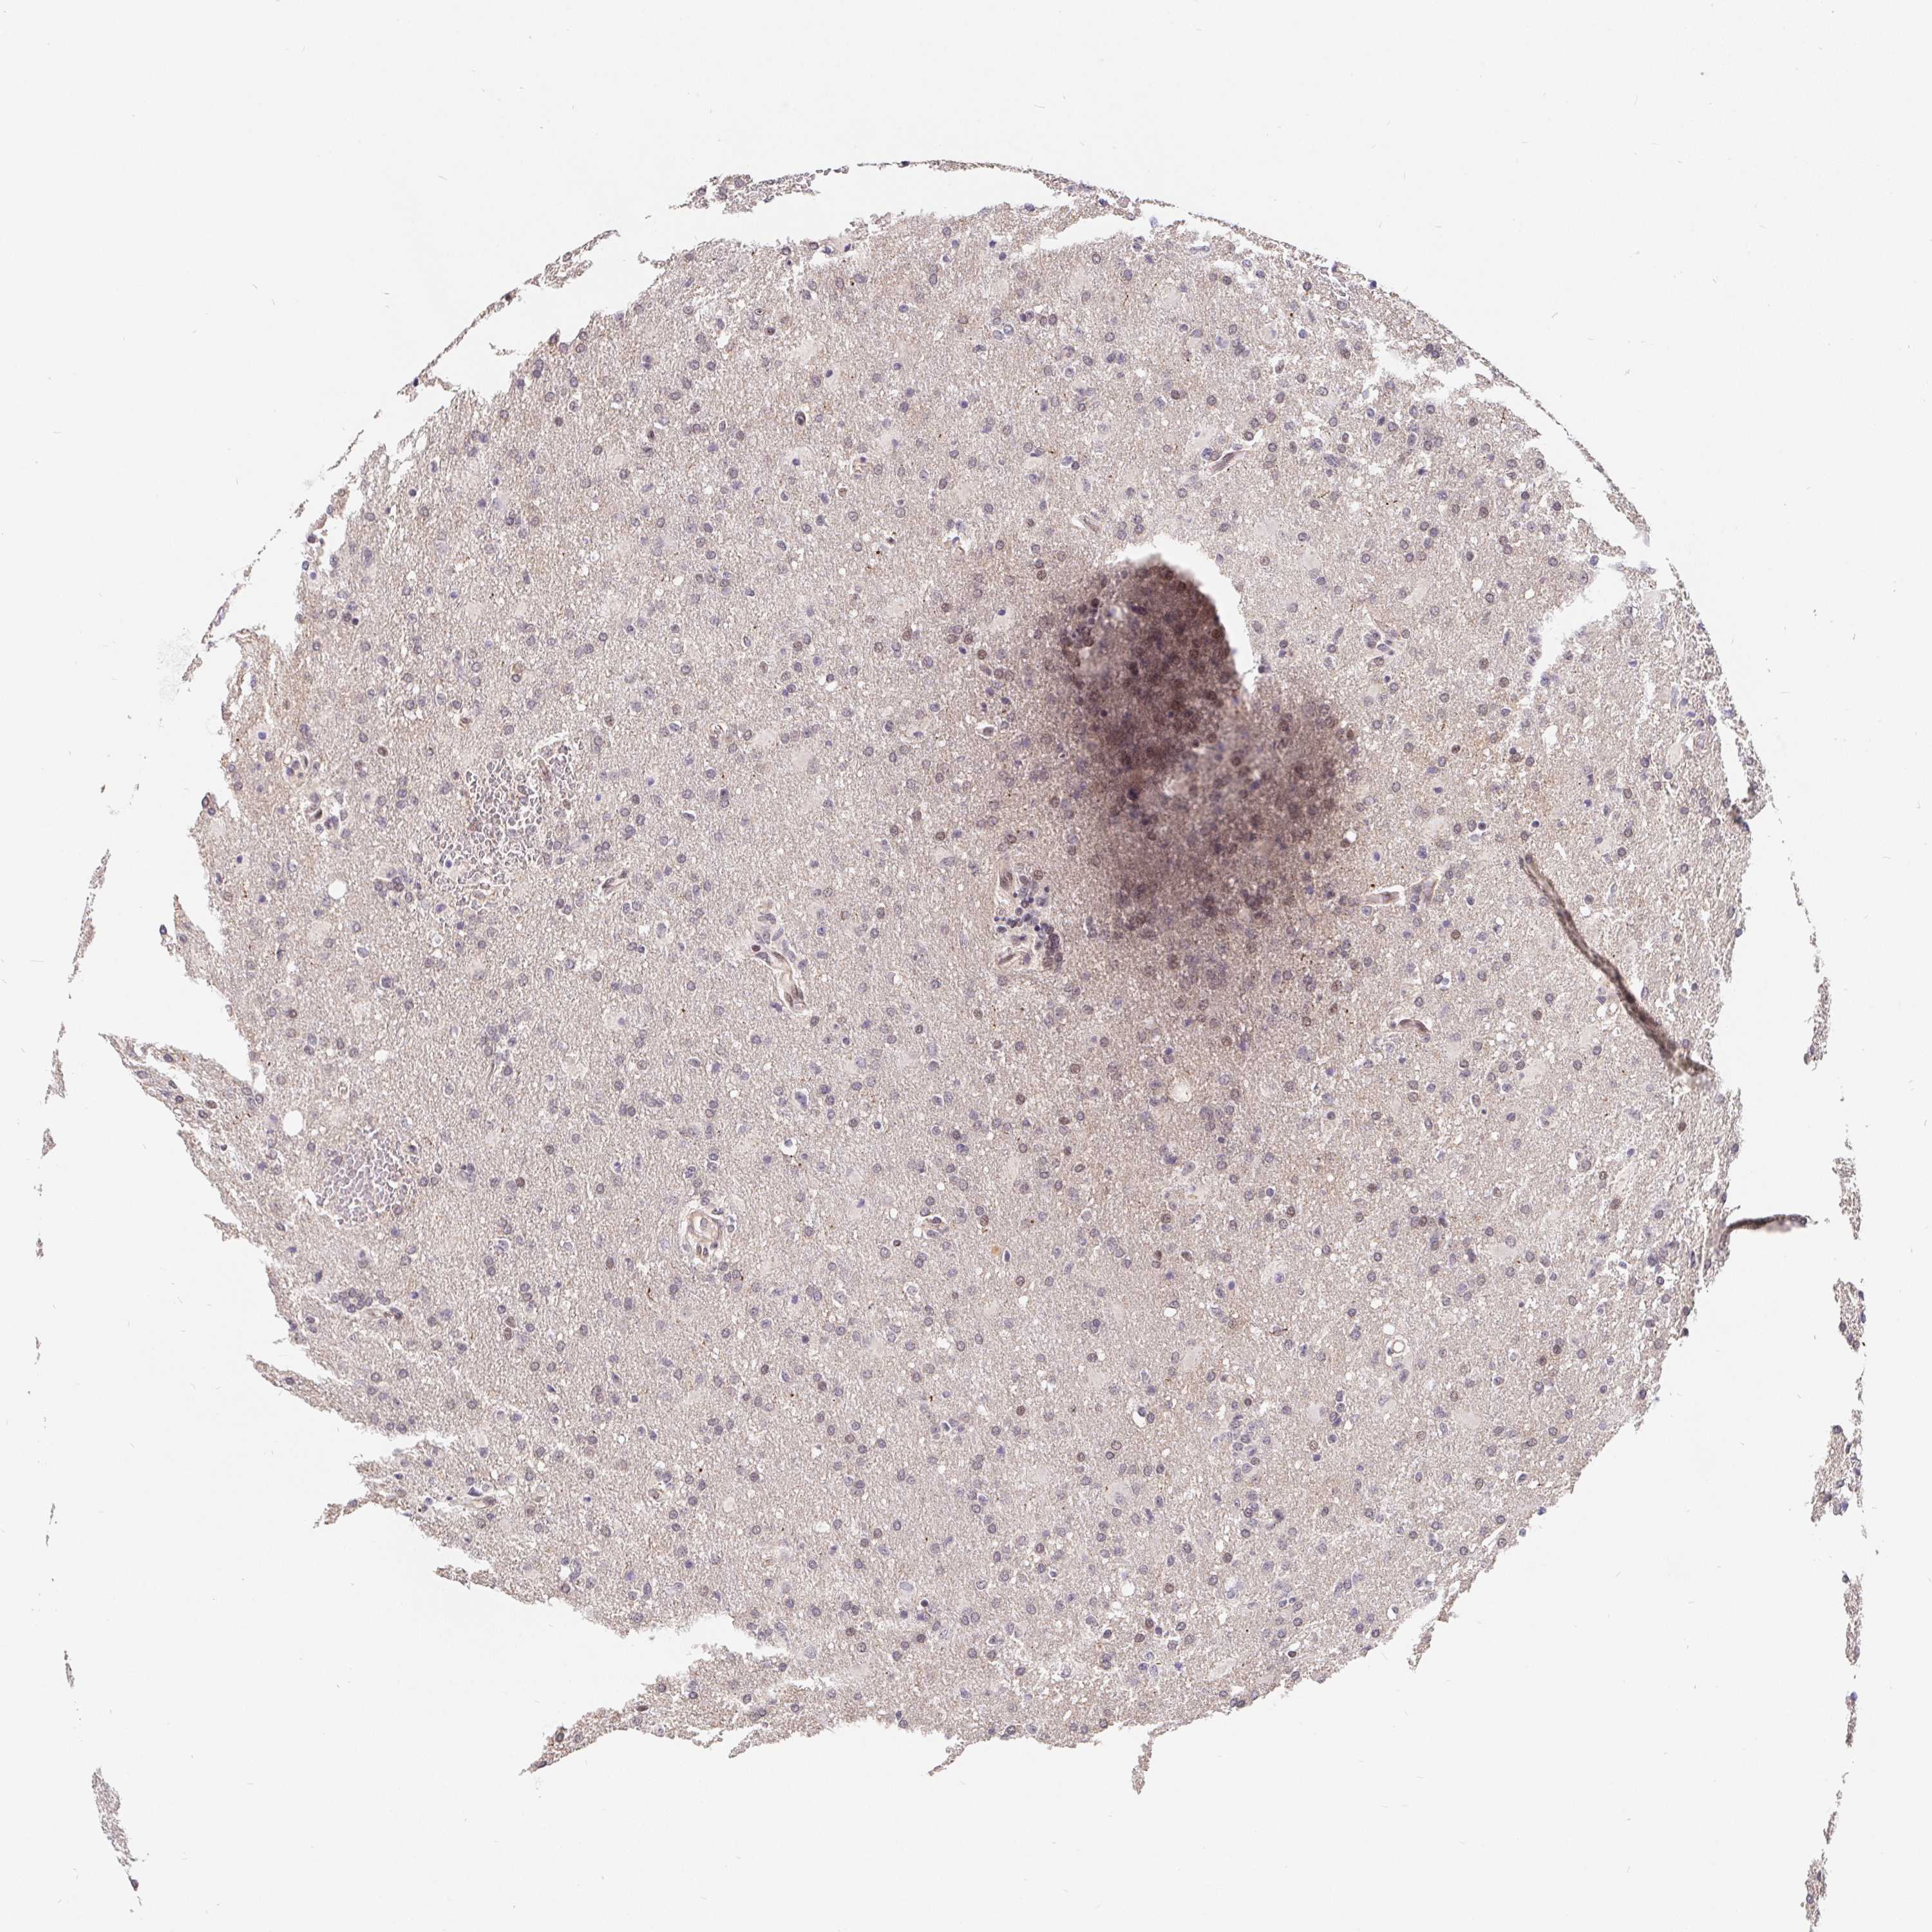

GLIOMA - Protein expressioni

A mouse-over function shows sample information and annotation data. Click on an image to view it in a full screen mode. Samples can be filtered based on level of antibody staining by selecting one or several of the following categories: high, medium, low and not detected. The assay and annotation is described here.

Note that samples used for immunohistochemistry by the Human Protein Atlas do not correspond to samples in the TCGA dataset.

Antibody stainingi

Antibody staining in the annotated cell types in the current human tissue is reported as not detected, low, medium, or high, based on conventional immunohistochemistry profiling in selected tissues. This score is based on the combination of the staining intensity and fraction of stained cells.

Each image is clickable and will lead to virtual microscopy that enables deeper exploration of all samples and also displays staining intensity scores, fraction scores and subcellular localization as well as patient and tissue information for each sample.

Antibody HPA064323

Antibody CAB002608

Staining

High

Medium

Low

Not detected

Intensity

Strong

Moderate

Weak

Negative

Quantity

>75%

75%-25%

<25%

None

Location

Nuclear

Cytoplasmic/membranous

Cytoplasmic/membranous,nuclear

Glioma, malignant, Low grade

Glioma, malignant, High grade